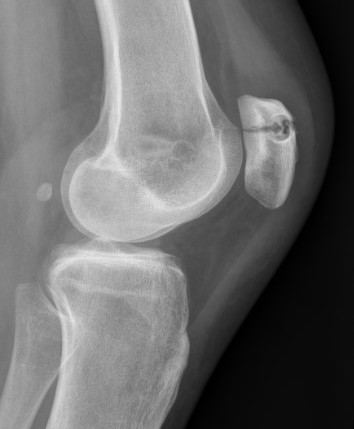

2. Perform TTT (if TTTG > 20)

- incision over TTT

- medialise at least 1 cm

- ensure some element of Fulkerson / anteriorise

- can distalise if patella alta

- secure with screws (2 x small fragment usually sufficient)

- reassess stability